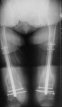

Attached are few examples from our Hospital:

A. Difficult reductions, even in retrograde nailing (my preference, easier control of "small" distal fragment) and it is much, much harder to do it anterograde (Alex, do you have one good case in your collection of anterograde nailing in very distal fractures - as you have suggested that I

should have done it in my previously posted case?

Malpositioning is much too common (recurvatum, varus - valgus).

B. Fixation loosening: distal cutting of the nail, non-unions do happen (cases attached).